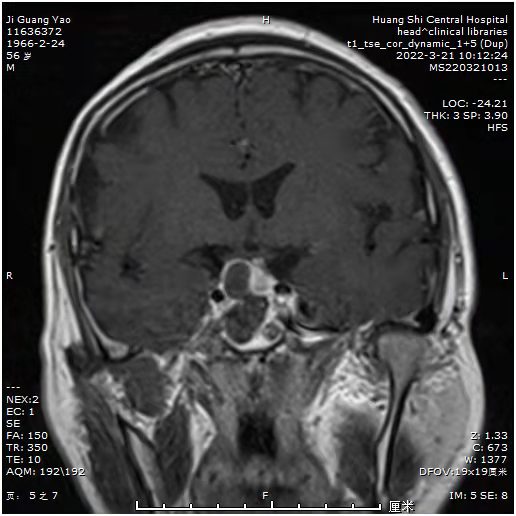

患者近期视力明显下降,一侧视力只有0.1,而且感觉眼部肿胀不适。MRI:发现鞍区占位。常规CTA,发现鞍区小动脉瘤!如果先处理动脉瘤,介入需支架辅助,术后需口服抗凝药物,近期3个月内,不能手术。患者必将失明!怎么办?和患者及科室血管介入组沟通后,患者意愿强烈,先行垂体瘤手术,做好术中动脉瘤破裂可能,带上动脉瘤夹,备用。

术后显示肿瘤切除满意,正常垂体及垂体后叶后叶保留,术后患者诉视力明显改善。眼睛暴胀感消失。视力基本正常范围。